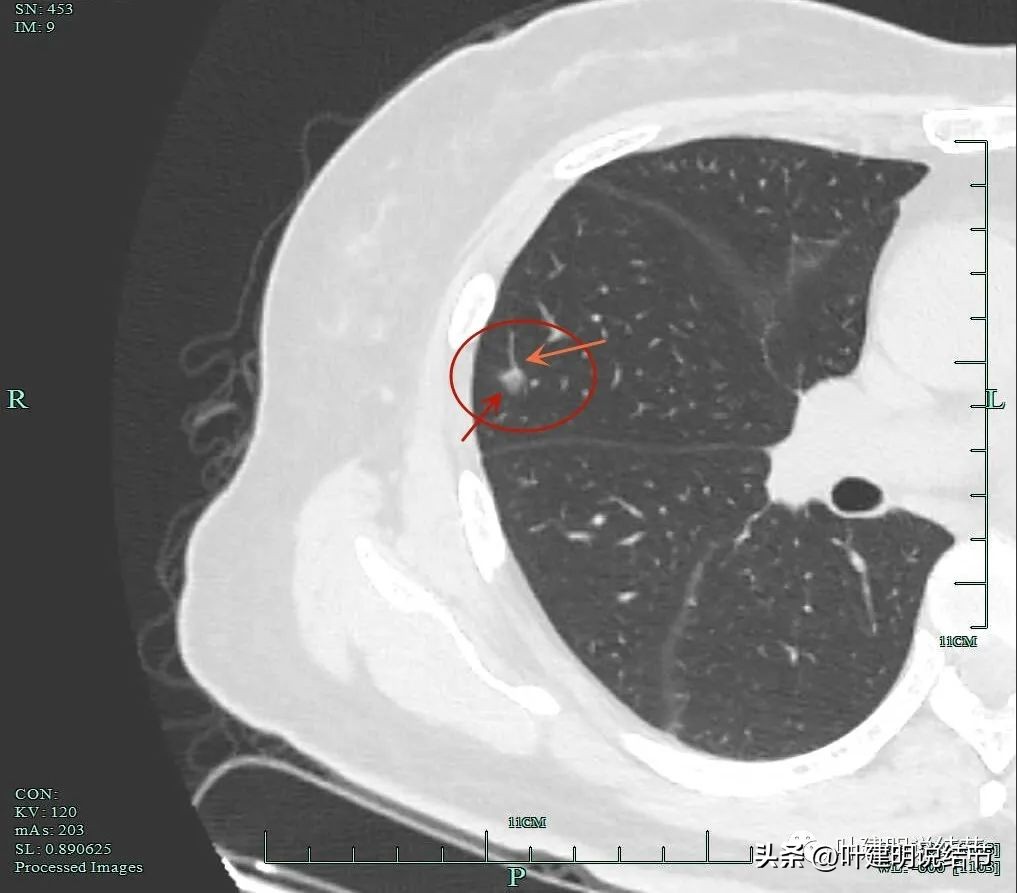

靶扫描重建图像显示了病灶明显的血管进入(如桔色箭头所示),灶内似见进入血管的穿行,而且显得毛糙与异常增粗。

血管征以及磨玻璃成分,病灶轮廓与瘤肺边界清。我们见进入的这支血管是有异常增粗的,它不是越往远心端越细,而且基本同样粗细走向病灶,到了病灶内部后显得散开来,密度反而更显高点。

灶内明显增粗毛糙的血管走行,磨玻璃成分轮廓清。